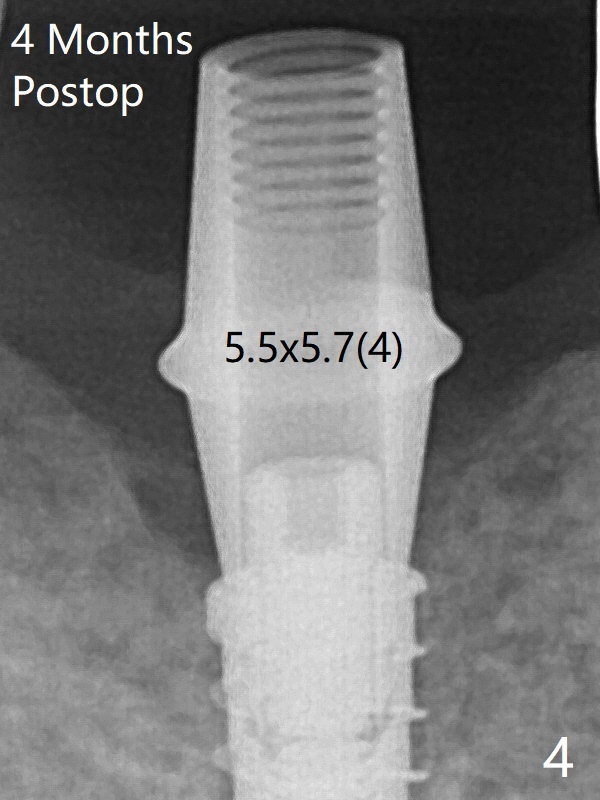

There is crestal bone loss 4 months postop (Fig.3,4).  It appears that the implant was placed excessively deep.